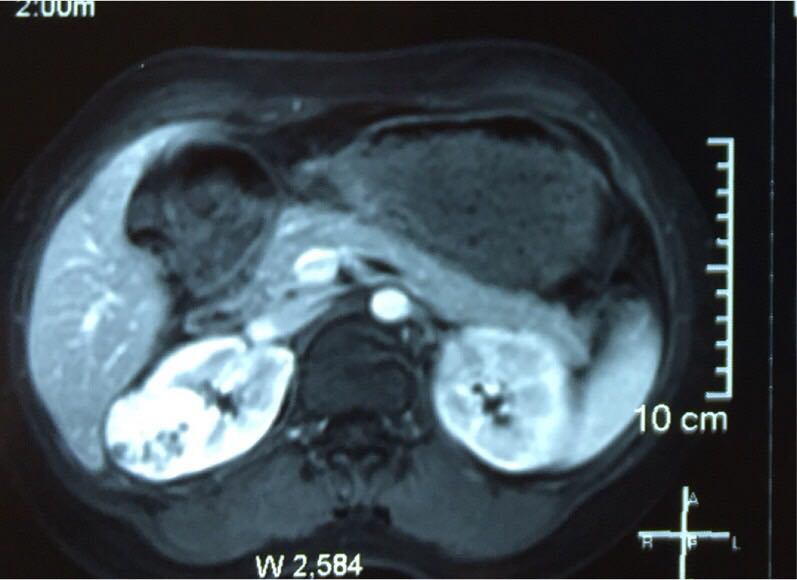

肾癌 ( renal carcinoma )